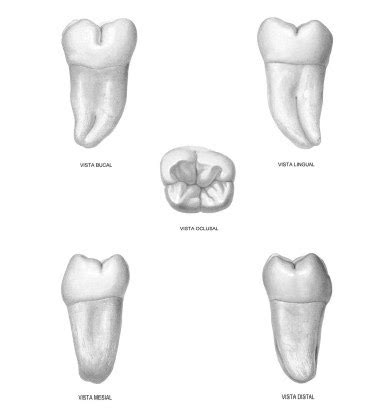

Existen cuatro cordales. Si dividimos la boca en cuadrantes, hay un cordal en cada uno de ellos. La situación de los cordales es la última dentro de la arcada dental. Son los últimos en salir y con la última posición. Es por ello que resulta muy importante durante su erupción mantener muy buena higiene oral, ya que de por sí es una zona que cuesta mantener limpia.

Clasificación de las Cordales

Los cordales pueden clasificarse según su posición y estado de desarrollo dentro de la mandíbula:

- Cordales Erupcionados: Son aquellos que han salido completamente de la encía y están bien alineados con el resto de los dientes.

- Cordales Incluidos: Son los que no logran erupcionar porque están completamente cubiertos por la encía o el hueso.

- Cordales Semierupcionados: Se refiere a los que han erupcionado parcialmente.

- Cordales Impactados: Son los cordales que han intentado salir, pero están en una posición incorrecta, chocando contra otros dientes o el hueso.

- Cordales Ausentes: En algunas personas, no se desarrollan en absoluto, ya sea por razones genéticas o evolutivas.

- Cordales Supernumerarios: Aunque es raro, algunas personas pueden tener más de cuatro.

Cada tipo de cordal puede requerir un manejo diferente según los síntomas y su impacto en la salud bucodental.